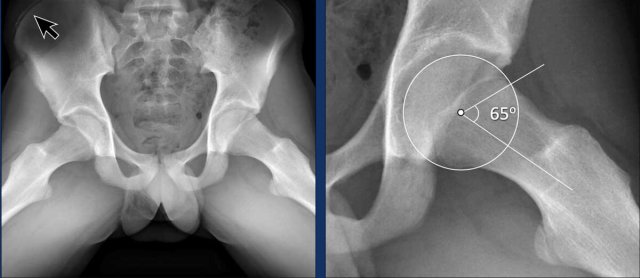

Alpha angle

The alpha angle is measured by drawing a circle through the femoral head, a line from the center of the femoral neck to the center of the femoral head, and then a line from the center of the femoral head to where the femoral head-neck junction intersects the circle.

If the angle is 60 degrees or more, it can be classified as Cam morphology. This measurement can be used both on conventional imaging as well as cross-sectional imaging - with cross-sectional imaging being more sensitive.

The threshold has been increased recently to 60 degrees to make it more specific.

Alpha angle measurement

The normal hip shows an alpha-angle far below 60º.

The hip with the Cam morphology has an alpha-angle far above 60º.

Of course, when the Cam morphology is as pronounced as in this case, angle measurements are unnecessary.